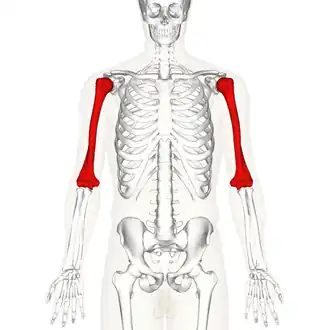

Position of humerus (shown in red) from an anterior viewpoint | |

The humerus (/ˈhjuːmərəs/; pl.: humeri) is a long bone in the arm that runs from the shoulder to the elbow. It connects the scapula and the two bones of the lower arm, the radius and ulna, and consists of three sections. The humeral upper extremity consists of a rounded head, a narrow neck, and two short processes (tubercles, sometimes called tuberosities). The shaft is cylindrical in its upper portion, and more prismatic below. The lower extremity consists of 2 epicondyles, 2 processes (trochlea and capitulum), and 3 fossae (radial fossa, coronoid fossa, and olecranon fossa). As well as its true anatomical neck, the constriction below the greater and lesser tubercles of the humerus is referred to as its surgical neck due to its tendency to fracture, thus often becoming the focus of surgeons.

Position of humerus (shown in red). Animation.

Position of humerus (shown in red). Animation. -